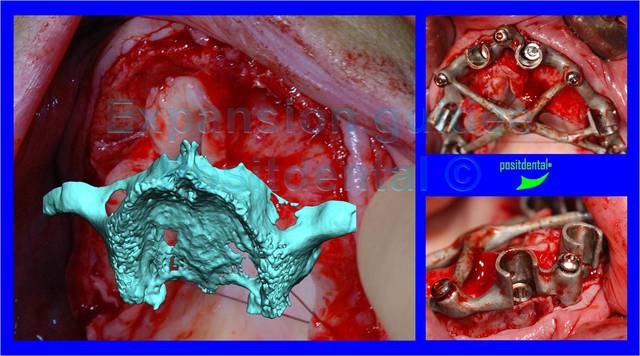

l'expansion guidée

Expansion guid e positdental vw7554 - Eugenol

Suite scan

Expansion guid e positdental 1 k5x8cz - Eugenol

Expansion guid e positdental 2 ziwwwn - Eugenol

Expansion guid e positdental 3 nbu2o1 - Eugenol